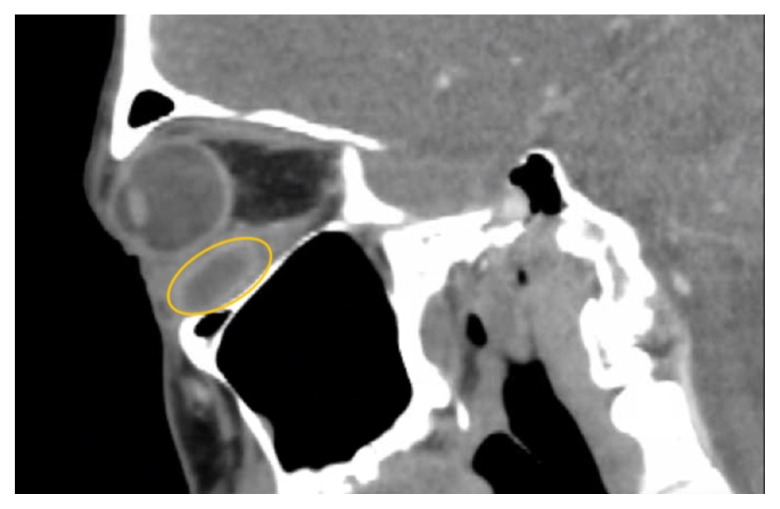

软组织感染,包括脓肿,是急诊科经常遇到的。然而,下直肌脓肿是罕见的,可能会提出独特的诊断和治疗挑战,由于缺乏文献病例。本病例报告强调了一名47岁男性,因急性耐甲氧西林金黄色葡萄球菌感染而出现左下直肌脓肿的治疗。影像显示明显的积液压迫左眼球,引起眼球运动受限和其他症状。尽管先前静脉注射抗生素,脓肿仍然存在。虽然静脉注射抗生素是治疗的重要组成部分,但本病例强调了单独使用这种方法的潜在不足,强调需要手术干预,如眼窝切开引流。本报告补充了关于下直肌脓肿的有限文献,并强调了进一步研究和临床关注以优化患者预后的必要性。主题:脓肿、软组织感染、眼外肌、化脓炎、耐甲氧西林金黄色葡萄球菌、眼球突出、复视、视力丧失。

Soft tissue infections, including abscesses, are frequently encountered in the emergency department. However, abscesses of the inferior rectus muscle are rare and may present unique diagnostic and therapeutic challenges due to the scarcity of documented cases. This case report highlights the treatment of a 47-year-old male presenting with an abscess in the left inferior rectus muscle due to an acute Methicillin-resistant Staphylococcus aureus infection. Imaging revealed a distinct fluid collection compressing the left globe, causing restricted ocular motility and other symptoms. Despite prior intravenous antibiotics, the abscess persisted. While intravenous antibiotics are an important component of treatment, this case highlights the potential insufficiency of this approach alone, emphasizing a need for surgical intervention such as orbitotomy for drainage. This report contributes to the limited literature on inferior rectus muscle abscesses and underscores the need for further research and clinical attention to optimize patient outcomes.